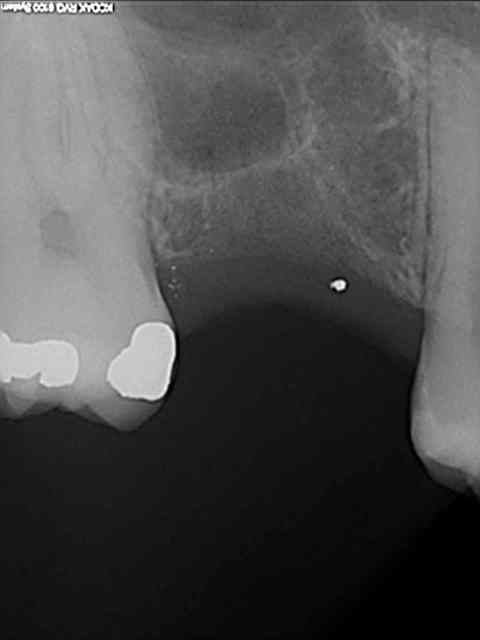

je sais pas si c'est un produit miracle, mais pour les sinus lift, c'est fantastique.

outre le fait de stabiliser un implant dans un sinus type SA4, pas de risque de voir partir le produit comme avec les granules de bioos et autres..

l'autre avantage est de ne pas avoir à mettre de membrane de recouvrement.

je suis donc hyper satisfait du résultat.

jugez plutôt...

quasiment 6 mois entre les deux interventions (sinus lift et mise à jour)

c'est surtout la qualité des trabéculations osseuses qui m'interpelle.

d'habitude, on voit toujours un peu de particules, ici, c'est vraiment top.